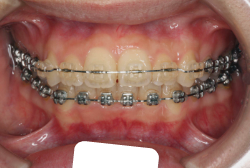

「ものがうまく噛めない」という主訴で来院したケースです。診断の結果、「骨格性反対咬合に伴う咬合不良+軽度叢生」と判明しました。原因としては特に下顎の左側が過成長したため、骨格性反対咬合になり、特に左側での噛み合わせが非常に悪くなっていると診断しました。初診時の写真を見ると、上下の正中線の大きなズレ、左側の噛み合わせの不良がはっきり分かります(黄色の矢印と緑の矢印は一致しているのが正しい状態です)。

そもそも、このような状態となっているのは骨の大きさに問題があるため生じていますので、場合によっては、「外科矯正」によって下顎の骨を外科的に縮めることで修正します。患者様が外科矯正をご希望されない場合は、従来ですと上下左右の小臼歯抜歯を行い矯正するのが普通です。

今回の患者様の場合は、「外科」も「小臼歯抜歯」も拒否されましたので、歯科矯正用アンカースクリュー(以下 アンカースクリュー)を用いて、下顎の歯列全体を後方に下げるという方法を取りました。

治療中の写真で、アンカースクリューより歯を後ろへ牽引しているのがお分かりいただけるかと思います。牽引を1年ほど続け、途中補助的に上下にゴムをかける(これを顎間ゴムと言います)手法なども追加し、全体で21ヶ月で治療を終えることが出来ました。

結局歯の本数を減らすことなく、すべてご自分の歯を残して、正しい配列と噛み合わせにすることができました。凸凹があまりひどくないため、簡単そうに見えると思いますが、このケースの初診の状態を見ると、熟練の矯正歯科医でも悩みのつきないケースです。まして、外科も出来ない、抜歯もイヤ、と言うことになると、従来の方法では治療不可能と考えられるのですが、アンカースクリューを使うことで最近は不可能が可能となってきました。